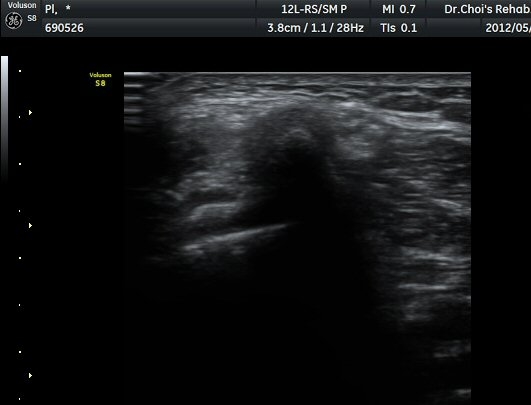

À­´Ù¸®(thigh) ¾Æ·¡ ºÎÀ§ ¿ÜÃø Ⱦ´Ü¸é°Ë»ç¿¡¼­ À̵ιڱ٠³»Ãø¿¡¼­ ÃѺñ°ñ½Å°æÀÌ Á¤»óÀûÀ¸·Î °üÂûµÈ´Ù(±×¸² 1, 2).

ŽÃËÀÚ¸¦ ¾Æ·¡·Î À̵¿ÇÏ¿© ºñ°ñµÎ ºÎÀ§±îÁö ÃѺñ°ñ½Å°æÀÇ ÁÖÇàÀ» µû¶ó ½Å°æÀ» È®ÀÎÇÏ¿´´Ù(±×¸² 3, 4).